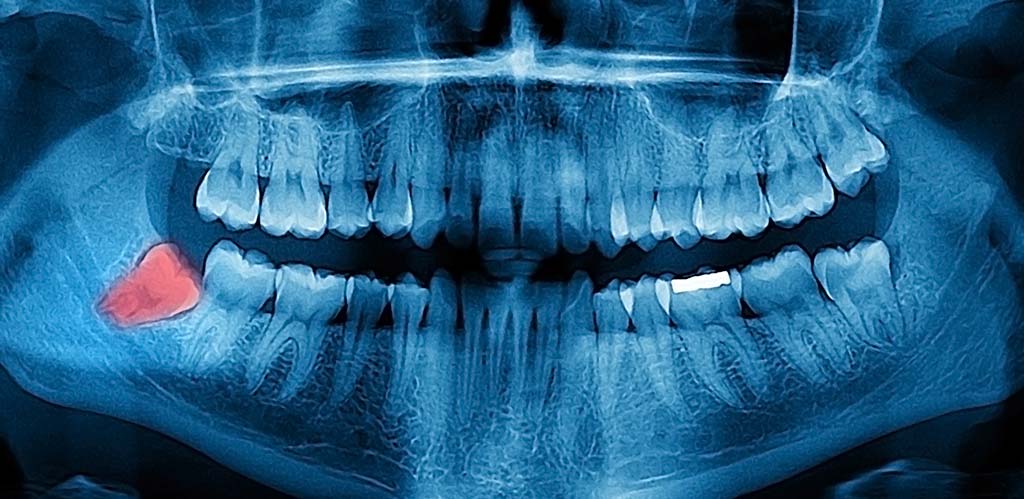

Panoráma röntgen: A hagyományos kis röntgen gépek csupán egy-két fog állapotáról készítenek használható képet. Éppen emiatt a panoráma felvételnek a legnagyobb előnye, hogy az egész fogsor állapotát megkaphatjuk egy képen.

Számos fogászati beavatkozás előtt ragaszkodnak röntgen kép készítéséhez. Két csoportra oszthatjuk a képeket, az egyik az úgynevezett digitális kis felvétel, a másik a panoráma felvétel. A digitális képeket akkor kérik a fogorvosok ha kimondottan egy fogat vizsgálnak meg. A panoráma röntgen semmiképp nem helyettesíthető ezzel a módszerrel, ugyanakkor kiegészíthetik egymást.

Gyakran előfordul, hogy egy rendelői hagyományos szájüregi vizsgálat nem elég ahhoz, hogy pontosan felmérjék a problémát, illetve kizárják annak az okát. Ilyen esetekben szinte kötelezően kérik a panoráma felvételeket, ugyanis elengedhetetlen a pontos diagnózis felállításához.